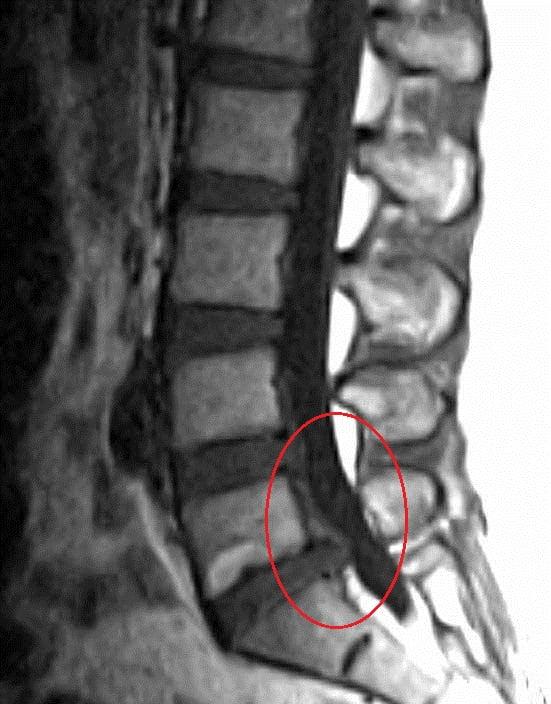

디스크(추간판 탈출증)과 MRI

대개 디스크는 추간판이라고 해서 영어로 disk라고 표현하긴 하지만 소견서에는 그 디스크 조직 안에 있는 수핵의 탈출 여부, 탈출 했으면 어느 정도 탈출했는지, 몇 번 척추사이에 탈출했는지, 그리고 탈출로 바깥쪽으로 되었는지, 안쪽으로 되었는지, 그리고 탈출의 정도가 어느 정도나 심한지를 표현하는 여러가지 전문용어로 되어 있습니다.

먼저 수핵은 nucleus pulposus라고 불립니다. 탈출되었다는 용어는 herniated라고 표현하고요. 그래서 수핵탈출증이라는 herniated of nucleus pulposus라는 병명이 씌여집니다.